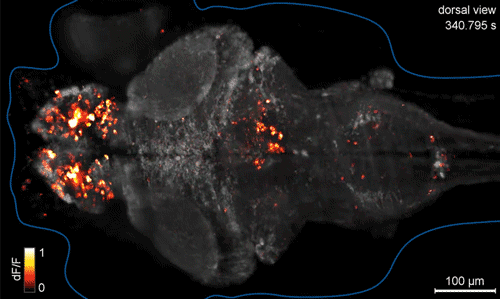

تصویر نورون در حال کار برای اوّلین بار

It looks like an oddly shaped campfire, but it is activity of individual neurons across a larval fish brain. It is the first time that researchers have been able to image an entire vertebrate brain at the level of single cells.

Brain function relies on communication between large populations of neurons across multiple brain areas, a full understanding of which would require knowledge of the time-varying activity of all neurons in the central nervous system. Here we use light-sheet microscopy to record activity, reported through the genetically encoded calcium indicator GCaMP5G, from the entire volume of the brain of the larval zebrafish in vivo at 0.8 Hz, capturing more than 80% of all neurons at single-cell resolution. Demonstrating how this technique can be used to reveal functionally defined circuits across the brain, we identify two populations of neurons with correlated activity patterns. One circuit consists of hindbrain neurons functionally coupled to spinal cord neuropil. The other consists of an anatomically symmetric population in the anterior hindbrain, with activity in the left and right halves oscillating in antiphase, on a timescale of 20 s, and coupled to equally slow

oscillations in the inferior olive.